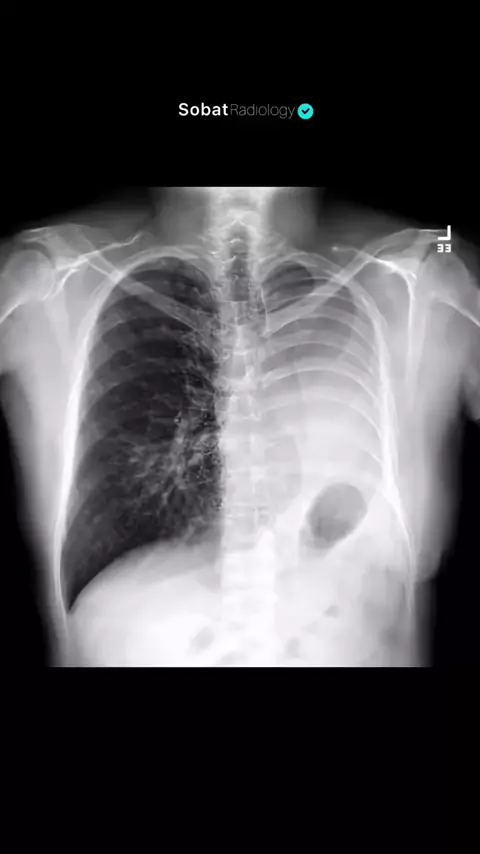

Pernahkah Anda mendengar istilah "paru-paru sebelah"? Ternyata, manusia memang bisa tetap hidup hanya dengan satu paru-paru. 🤯 Secara medis, kondisi ini sering kali disebabkan oleh prosedur Pneumonectomy, yaitu operasi pengangkatan salah satu seluruh bagian paru, seperti yang tampak pada hasil rontgen ini di mana sisi kiri telah diangkat. Pada gambaran radiologi pasca-operasi, ruang kosong tersebut (postpneumonectomy space) secara alami akan terisi oleh cairan, disertai tanda-tanda klinis sepe...